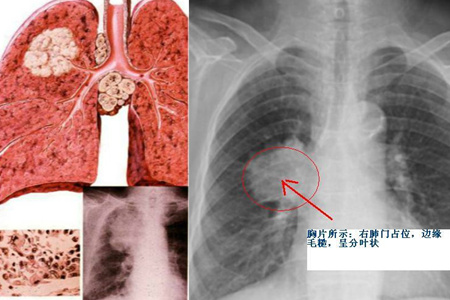

癌症我们应该不陌生,因为现在在我们身边,经常会听到某某某因为癌症而离世。在中国,恶性癌症可以说是致死率非常高的疾病之一。支气管肺癌大家应该或多或少有所耳闻吧,这个疾病主要是支气管和肺部因为受到外界的污染和刺激,导致肺部和支气管发生恶性肿瘤,到目前数据显示,该疾病是致死率最高的恶性肿瘤之一。

支气管肺癌的症状其实非常明显,如果是在癌症的早期,主要表现为咳嗽,痰中有血,有的患者会有气短等等症状,这个时候患者就需要到医院做一个胸外科检查,及时发现疾病。而到了中后期之后,患者的症状会明显加强,比如说咳嗽得更加剧烈,甚至会有呕血的现象,而且胸部会出现疼痛,气短也会更加严重,甚至爬一个小小的楼梯都会气喘吁吁。